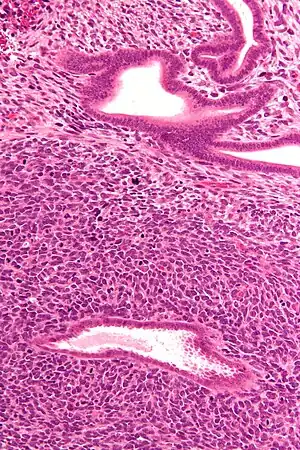

| Micrograph of a uterine adenosarcoma showing a mitotically active malignant stroma and benign glands. H&E stain. | |

Uterine adenosarcoma have, by definition, a malignant stroma and benign glandular elements. The World Health Organization (WHO) criteria have a mitotic rate cut point; however, this is often disregarded, as bland-appearing tumours with a low mitotic rate are known to metastasize occasionally.[2]